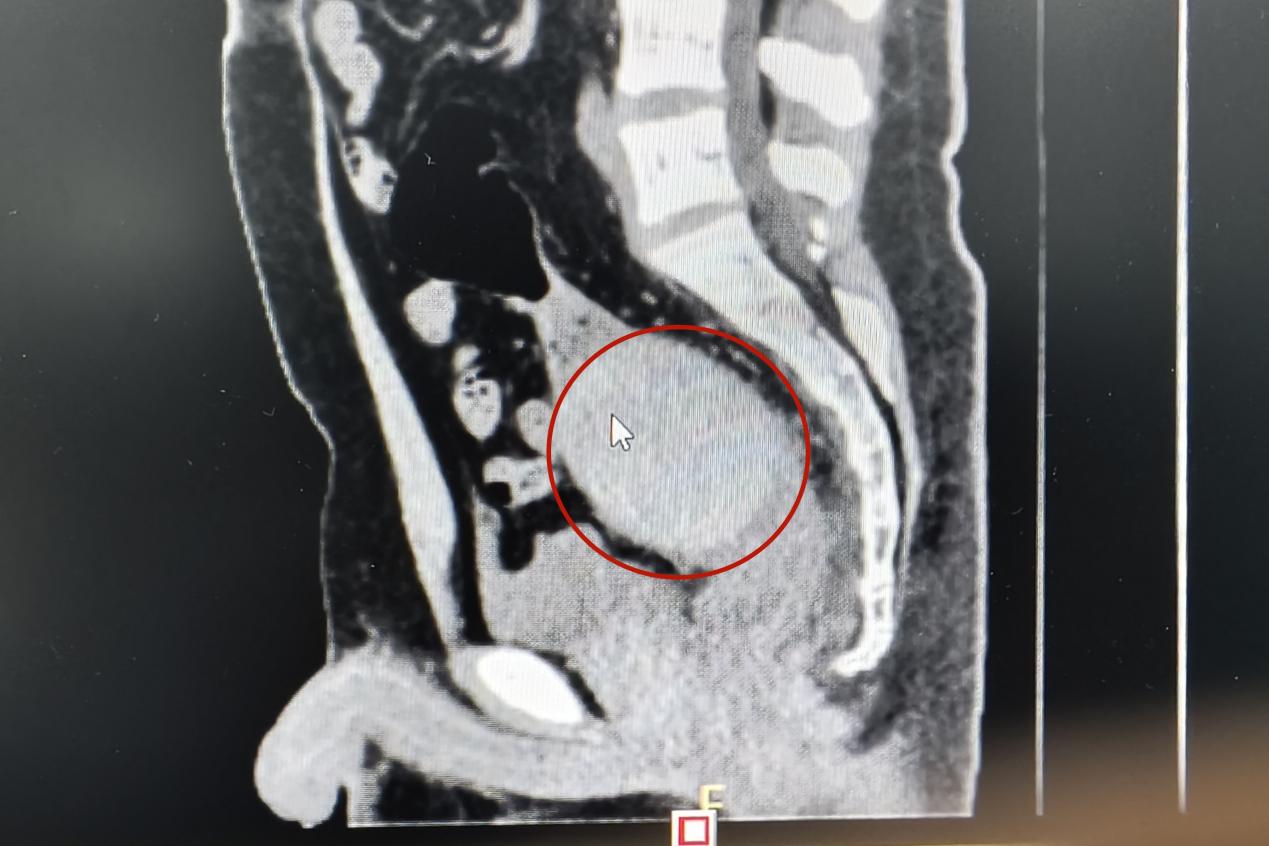

當天下午,一名青年男子來到衡陽市中心醫(yī)院肛腸外科門診就醫(yī),稱肛門內(nèi)有異物,肚子疼得很。李祥樂仔細詢問病情,男子卻總是支支吾吾??此?/span>表情痛苦,李祥樂便讓他躺到治療床上,對其進行了肛門指檢。“你這個異物卡得很深,指檢觸不到,需要馬上做個CT明確位置?!崩钕闃芬贿吀嬷颊咭贿呍儐?,“這個東西卡進去多久了?”得知是昨晚發(fā)生的事,李祥樂心頭一驚,卻表面平和地安慰患者道:“沒事的,到醫(yī)院來你就放寬心了,等檢查結果出來我們想辦法給你取”。CT結果顯示患者異物位于直腸與乙狀結腸交界處,位置特殊,加之卡頓時間長,取的過程中腸道破裂出血的風險隨之增加。“我可以嘗試給你經(jīng)肛門取,但是如果取不出來那就需要進行腹腔手術了”。

晚上8點,患者被推進了手術室。術中,患者在麻醉后肛門括約肌松弛,李祥樂仔細探查后,用一只手從腹部壓住異物,一邊叮囑患者配合作下排動作。由于異物表面光滑,器械夾取困難,為避免患者腸壁受到損傷,李祥樂將三根導尿管插入患者肛門中,通過往囊腔中注水使得腸壁擴張,在固定異物的同時為夾取構建了通道。經(jīng)過10多次反復夾取,異物被一點一點摳出,從指甲蓋大小的塊狀到整個與導尿管一起被牽拉拔出,整個手術進行了兩個小時。